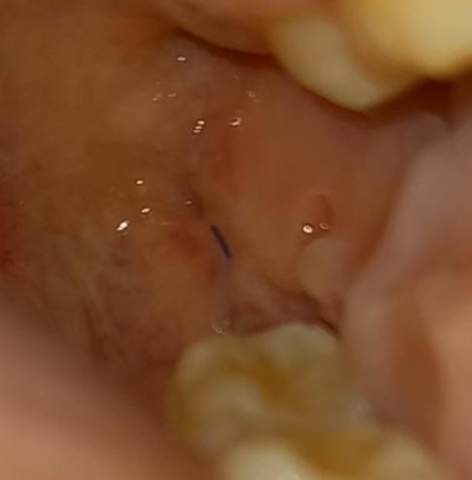

Bei Wundnähten durch Weisheitszahn-Operationen oder anderen chirurgischen Eingriffen kann das Fadenmaterial häufig schon nach einigen Tagen entfernt werden. Sprich der größte Teil des Fadens ist noch im Zahnfleisch. In dieser Zeit bitte keinen Alkohol Kaffee Cola oder schwarzen Tee trinken.

Beim Spülen sind meistens auch rote Verfärbungen zu erkennen also es blutet nicht stark sondern nur sehr sehr wenig aber dafür recht oft. Da stellt sich mir die Frage wie der Zahnarzt nun die Fäden ziehen will.